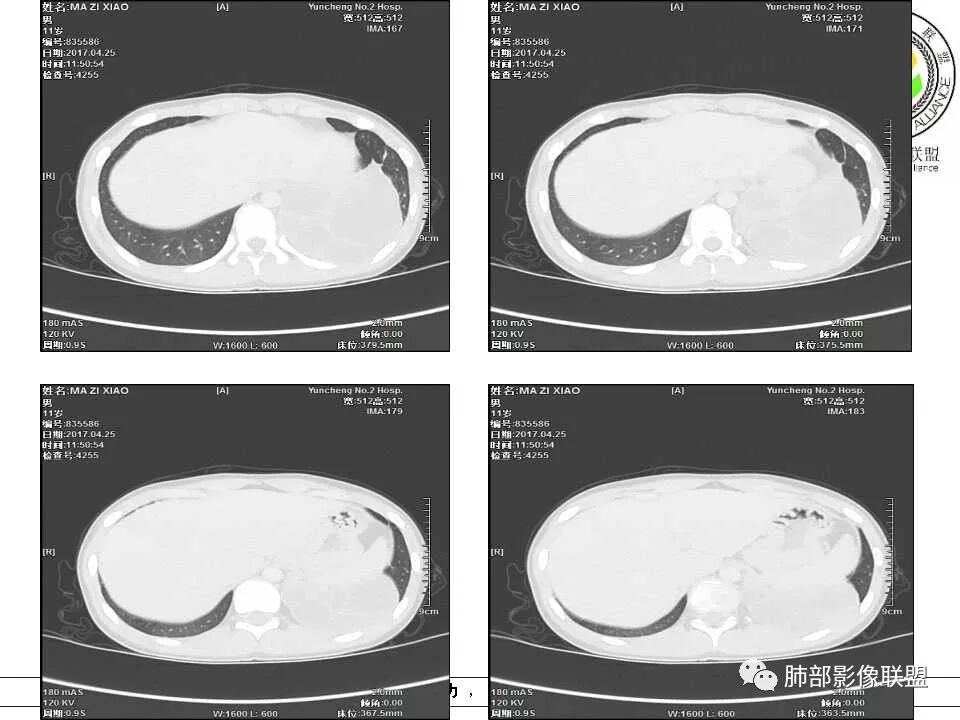

病例提供:运城市第二医院  王崇军

肺隔离症,供血动脉来源腹主动脉

肺隔离症 膈下腹主动脉供血 肺静脉引流 多房改变支气管扩张积液?

左下肺囊性占位,多发分隔,增强分隔及边缘强化,腹主动脉供血,考虑肺隔离征。

儿童左下肺囊性占位,多发分隔,增强分隔可见强化,腹主动脉供血,肺隔离征。

左肺下叶病灶,囊性为主,内见分隔,边界清晰,首先考虑良性病变,增强可见体循环供血,考虑肺隔离症

儿童,左下病变,边界清,囊性,分隔明显,体循环供血,肺隔离症。

左下肺囊性变,内有分隔,体循环供血,支持隔离症。

病灶位于左肺下叶,边界清,囊性,内见分隔,增强可见体循环供血,支持肺隔离症。

左下肺囊性团块灶,多发分隔,增强分隔及边缘强化,主动脉供血,考虑肺隔离症,叶外型。

左下肺囊状影,内有分隔,体循环供血(腹主动脉),肺静脉回流,考虑隔离症

左肺下叶多房囊性病灶,主动脉分支供血,肺静脉回流,符合肺段隔离症,应该是肺外型吧

左肺下叶囊性占位,腹主动脉供血,肺动脉引流,考虑肺隔离症。

左肺下叶囊性变,可见多发分隔,增强后分隔及边缘可见强化,并可见降主动脉分支进入,考虑叶外型肺隔离症

左下肺肿块,内部见多分隔,囊性密度,增强见腹主动脉分支、肺动脉供血,考虑肺隔离症,鉴别支气管囊肿

儿童,左下肺多房囊性占位,增强分隔强化,腹主动脉供血,肺隔离征。

11岁男患,左肺下叶见囊性病变,期内见分隔,增强扫描见强化,供血血管清晰,考虑肺隔离症,不除外多房性囊性病变。

男,11岁,左肺下叶囊性包块,形态不规则,内有分隔,包膜及分隔明显强化,主动脉供血,肺静脉引流,基底段支气管显示不清,首先考虑常见病肺隔离症,支气管囊肿不排除

电话随访,患者在西安某医院手术,为肺隔离症,供血两支动脉,均来自腹主动脉,引流入肺静脉。